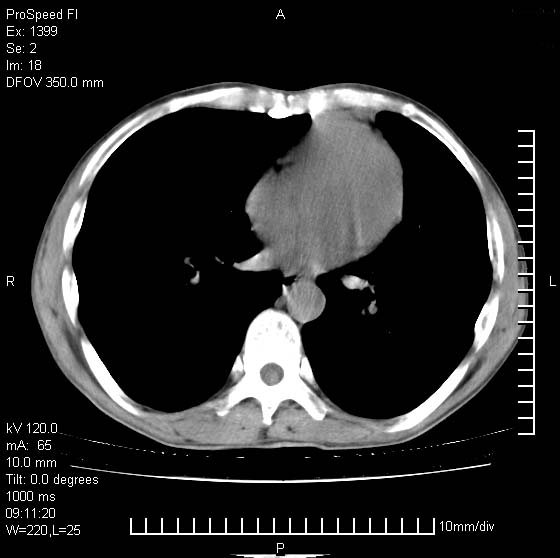

以下是引用卜一在2007-1-19 9:55:00的发言:[br]左肺沿胸膜下巨大肿块影,边缘呈分叶征,纵隔内见肿大淋巴结,右肺内另见一不规则结节影 .考虑:左肺周围性肺癌伴纵隔 右肺内转移.

以下是引用rgsyyf在2007-1-19 11:05:00的发言:[br]左肺上叶见形态不规则巨大软组织肿块影,边缘呈分叶征,纵隔内隆突下见肿大淋巴结,右肺内另见一不规则结节影 .考虑:左肺周围性肺癌伴纵隔即右肺内转移.